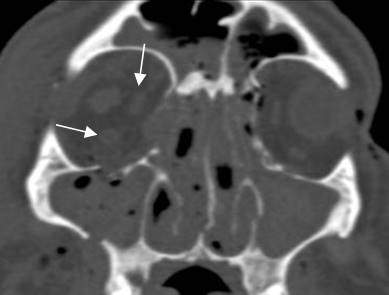

Fig 215 B. Fractura de órbita.

A: TAC coronal en ventana de tejido y B: TAC coronal en ventana de hueso.

Fractura deprimida en el piso de la órbita. Hay herniación de la grasa, pero el recto inferior mantiene su posición. (Flecha gruesa).